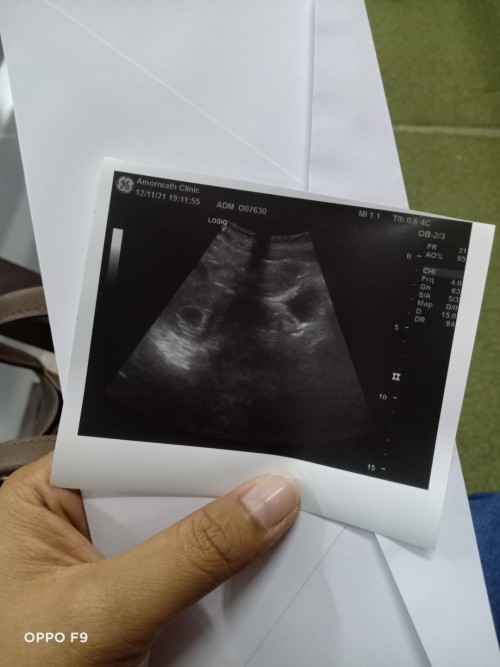

เราก็ได้8วีคไปซาวก็ไม่เจอน้องเหมือนกันค่ะแต่ก็ยังแพ้ท้องเหมือนเดิมมีอาการปวดหน่วงท้องน้อยแต่ไม่มีเลือดออกค่ะจิตตกอยู่เหมือนกันค่ะ

แม่บ้านนี้ท้องได้ 8w+6d ซาวด์เจอแต่รกไม่เจอถุงตั้งครรภ์ ยังแอบคิดและกังวลอยู่เหมือนกันคะ แต่หมอนัดให้ไปซาวด์อีกรอบคะ อันนี้ก็รอลุ้นคะ

ของเราฝากคลีนิคค่ะครั้งละ1,500 พร้อมซาว4มิติ ไม่แน่ใจว่าโรงพยาบาลอาจจะมีบ้างที่รับสิทธิ์ประกันสังคมนะคะ ลองหาข้อมูลในกูเกิ้ลอีกทีค่ะ